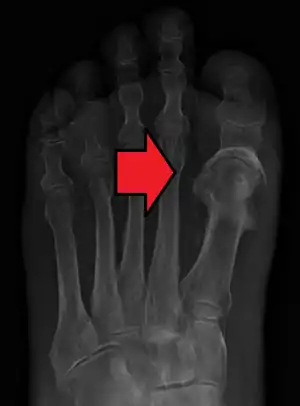

Osteomyelitis

Osteomyelitis (OM) is an infection of bone.[1] Symptoms may include pain in a specific bone with overlying redness, fever, and weakness.[1] The long bones of the arms and legs are most commonly involved in children, while the feet, spine, and hips are most commonly involved in adults.[2]

| Osteomyelitis of the 1st toe | |